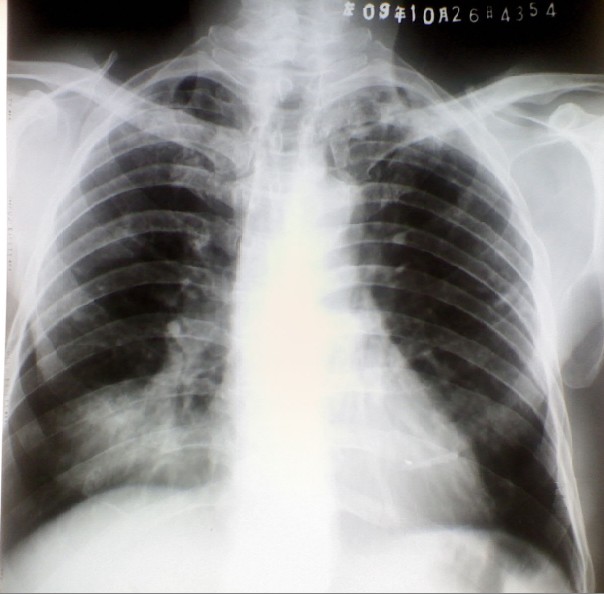

男。65岁。胸闷,现在右侧胸痛7天余。无发热

右下肺占位性病变,肺癌可能性大,建议ct。

两上增殖病灶(左甚),右下病灶考虑占位可能性大,感染或斜裂积液不排除。

双上肺少许增殖灶,右下肺占位性可能,支持肺部进一步检查。

双上肺可见斑片状阴影,部分密度均匀,边界清。部分密度不均,边界不清。右肺下野近心膈角处可见大片密度增高影,边界不清,密度不均。考虑双肺结核。右下肺感染。不排除占位可能。建议ct检查

双上肺陈旧性结核病变;

右下肺阴影,考虑占位病变可能性大,建议ct进一步查。